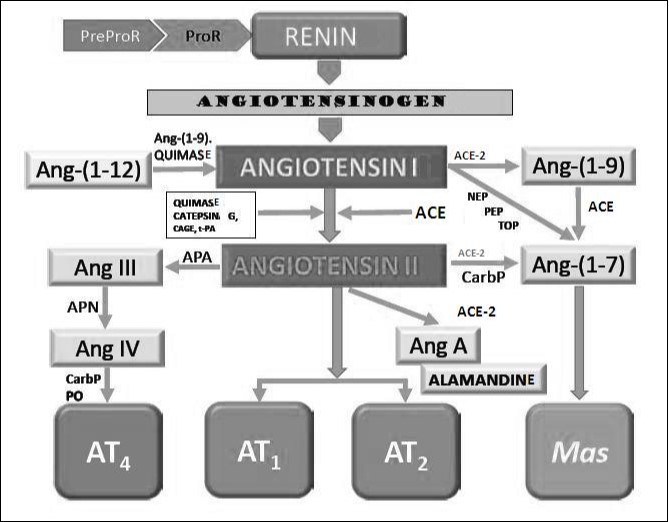

Renin cleaves to angiotensinogen,Figure 3 produced and released into the circulation by the liver into angiotensin I. ACE, widely present along the vasculature and into the renal tubules, cleaves angiotensin I giving Ang II. Ang II, is also a potent vasoconstrictor, activates the synthesis of aldosterone and its release of the zona glomerulosa of the adrenal cortex, with secondary increase in circulation of the same32. Aldosterone binds to the receptor of mineralocorticoids in the epithelial cells of the duct collector of the nephron, inducing the excretion of potassium and sodium retention (RM).

Figure 3.Classical and non-classical enzymatic production of angiotensin pathways